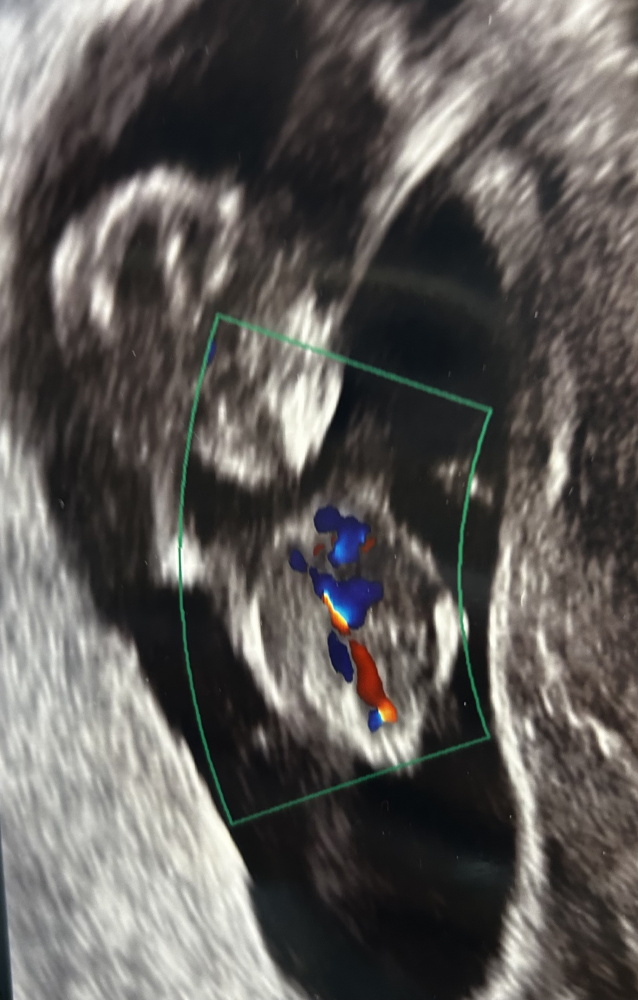

Ultraschall von oben - 2 Striche Mädel oder Bub?

Hallo Zusammen, das Bild ist in der 12. SSW entstanden. Man schaut von oben auf unseren Krümel. Es sind zwei sehr deutliche Striche. Jemand Erfahrung ob dies eher Mädchen oder Junge ist?